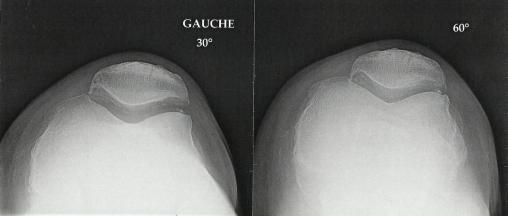

Collection P. Frances La radiographie met en évidence un genu varum, une importante gonarthrose fémoro-patellaire et un fin liseré calcique témoignant d’une chondrocalcinose articulaire.